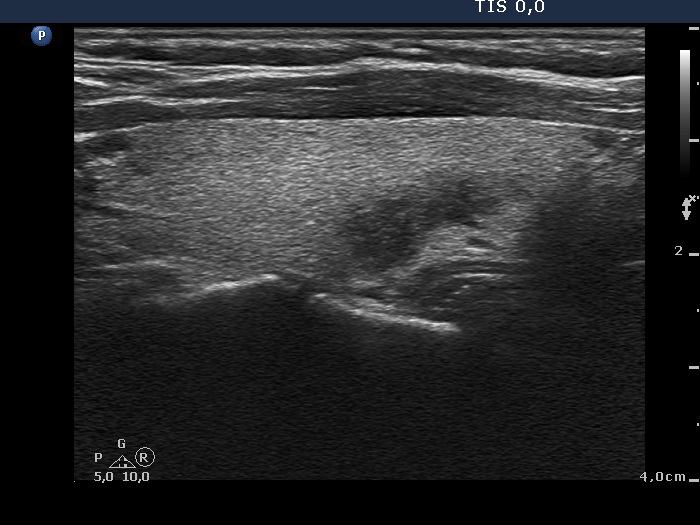

Follow-up 6 months after the first visit (3rd row of images):

Clinical presentation: The patient had no complaints.

Palpation: no abnormality.

Laboratory tests: TSH 2.06 mIU/L, FT4 13.3 pM/L, CRP 0.3 mg/L.

Ultrasonography: The pattern of the entire thyroid became almost completely normal. Only small hypoechoic areas were observed.

Suggestion: TSH in six months, in the event of pregnancy at once.